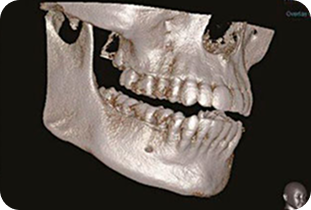

Точная диагностика - залог успешного лечения

Почувствуйте разницу между понорамным снимком и 3D томографией.

Компьютерная 3д томография

На компьютерной томографии видно, что начал развиваться гайморит, вызванный заболеванием зубов, образовавшимися кистами.

Оборудование нового поколения

Стоматология на Марата-31 оснащена рентген-кабинетом, в котором, помимо стандартных прицельных и панорамных снимков зубов, проводится 3D компьютерная томография всей полости рта. Томография в 3D формате позволяет диагностировать различные челюстно-зубные дефекты и максимально точно поставить диагноз. Для тех пациентов, кто боится уколов, в нашей клинике применяется компьютерная анестезия. Компьютер вводит анестетик с определенной скоростью и под низким давлением, благодаря чему болезненные ощущения практически отсутствуют.Также в стоматологии на Марата-31 применяется специальная лампа (аппарат АФС) для диагностики воспалительных процессов, предраковых заболеваний и ранних стадий рака слизистой полости рта.